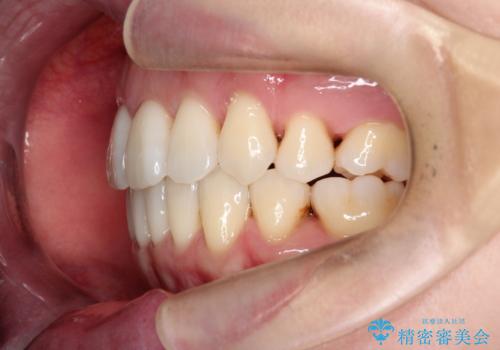

【抜歯ケース】前歯のガタガタをインビザラインで治療

- 前歯のガタガタを主訴に来院されました。

抜歯が必要なケースでしたが、インビザラインでの治療を希望されワイヤーを使用せずに治療を完了しております。

抜歯を伴う矯正治療はマウスピース矯正よりもワイヤー矯正の方がメリットが多いです。当院で抜歯を伴うマウスピース矯正を希望される場合は、場合によってワイヤーを使うことを了承していただいた上で治療を行なっています。